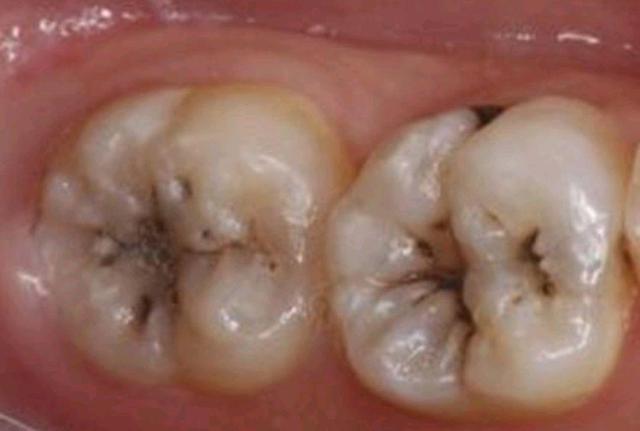

后槽牙牙齿发黑图片,牙齿凹槽上面有黑色

牙齿上的黑线是蛀牙吗

牙齿上面这种黑色的需要补吗

牙齿表面黑色的点或线段就是窝沟龋啦

发黑的牙齿都是蛀牙吗

最里面的大牙发黑图片